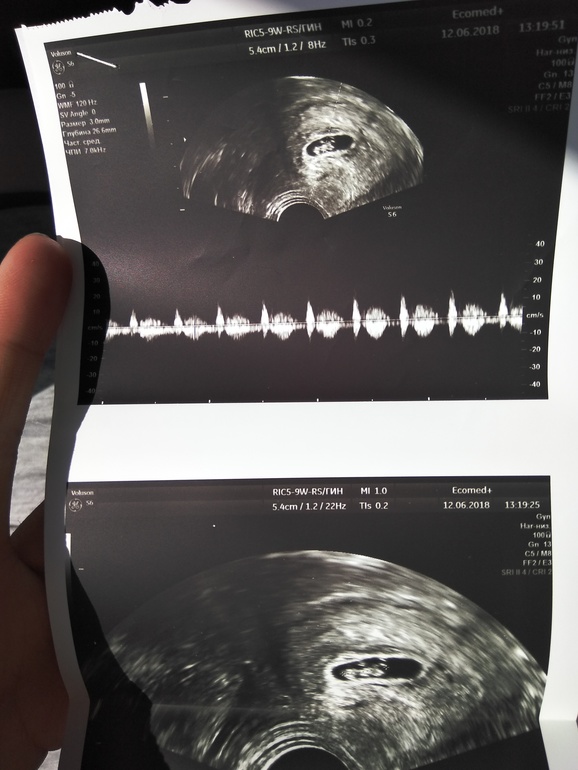

Подтвердили беременность 6-7 недель. КТР - 10,5 мм. Прикрепился малыш по передней стенке в срединном положении. Сердцебиение послушали 😍 Не могу до сих пор поверить...у нас будет второй! Мне и страшно и очень радостно) Хочется сына для полного счастья😅

А это наш малыш😀